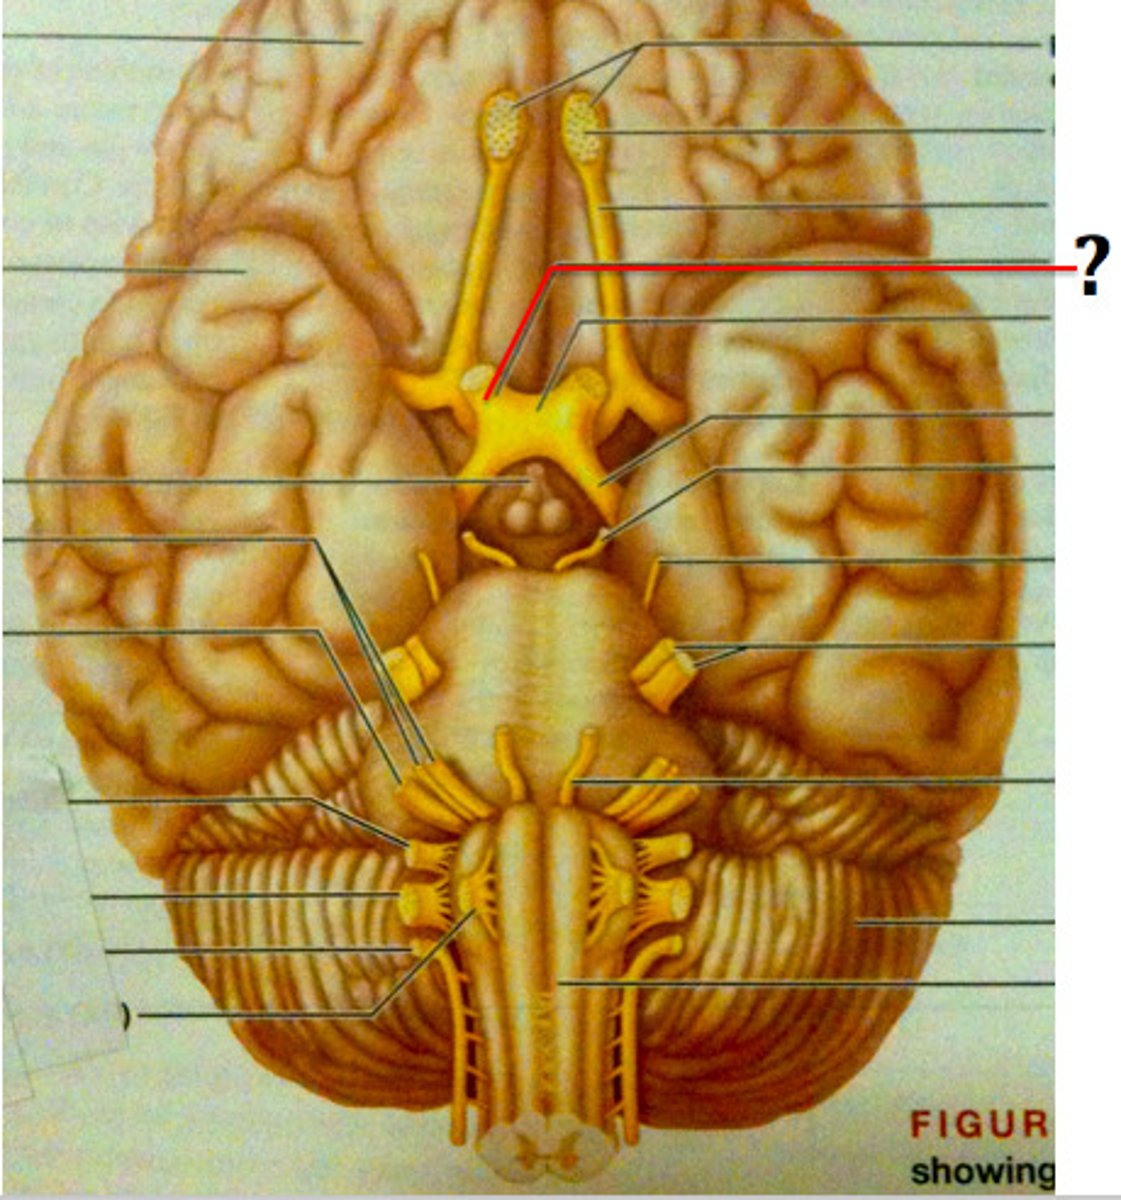

olfactory nerve (CN I)

Sensory cranial nerve related to smell

olfactory tract

primary olfactory cortex (uncus)

optic nerve (CN II)

Sensory cranial nerve related to vision

optic chiasm

point at which optic nerve fibers cross in the brain

optic tracts

the continuation of the optic nerve fibers beyond the optic chiasma